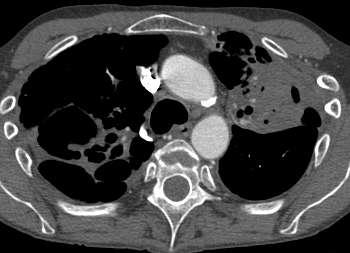

文献也报告了一些新的应用如: 活动性肺结核及大咯血

Onyx 栓塞导致肺毒性

栓塞后5小时发生咯血,但没发现血氧饱和度下降。 栓塞开始前必须检查的项目包括,推荐最大的注射率进行注射。推荐最大的容积注射。检查微导管或真腔容积量。这一容量必须充盈慢血管栓但塞。围手术期还要坚持的是监测血氧饱和度。 除此以外Onyx胶栓塞仍然存在缺血并发症(2.1%,5/233)和意外非靶血管的栓塞(3.9%,9/233)。